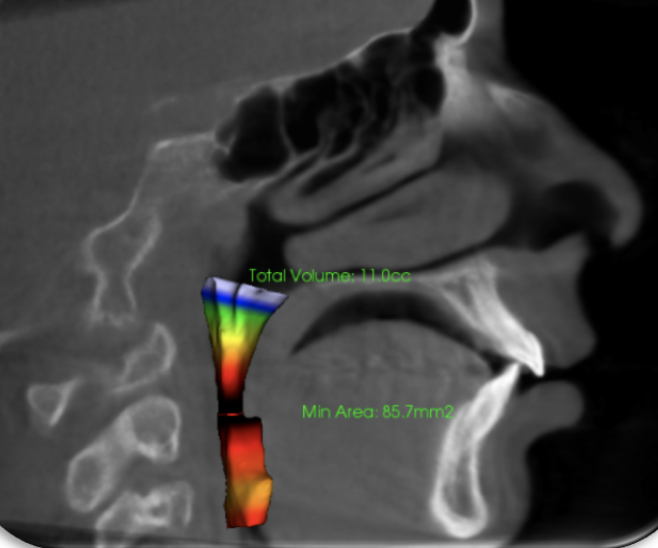

Expansion and lower jaw andvancement opened his airway from 11 to 3o CC.

Before

After

This patient was treated without extractions!